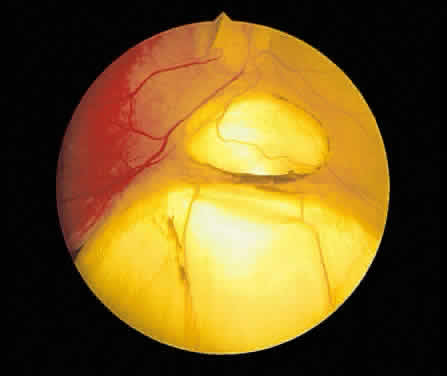

in the region of the ciliary body.  Fig. 16. Fundus photograph of a disciform macular scar, white because of fibrosis

and atrophy of the pigment epithelium. A broad, C-shaped, fresh hemorrhage

within the sensory retina surrounds it. Fig. 16. Fundus photograph of a disciform macular scar, white because of fibrosis

and atrophy of the pigment epithelium. A broad, C-shaped, fresh hemorrhage

within the sensory retina surrounds it.